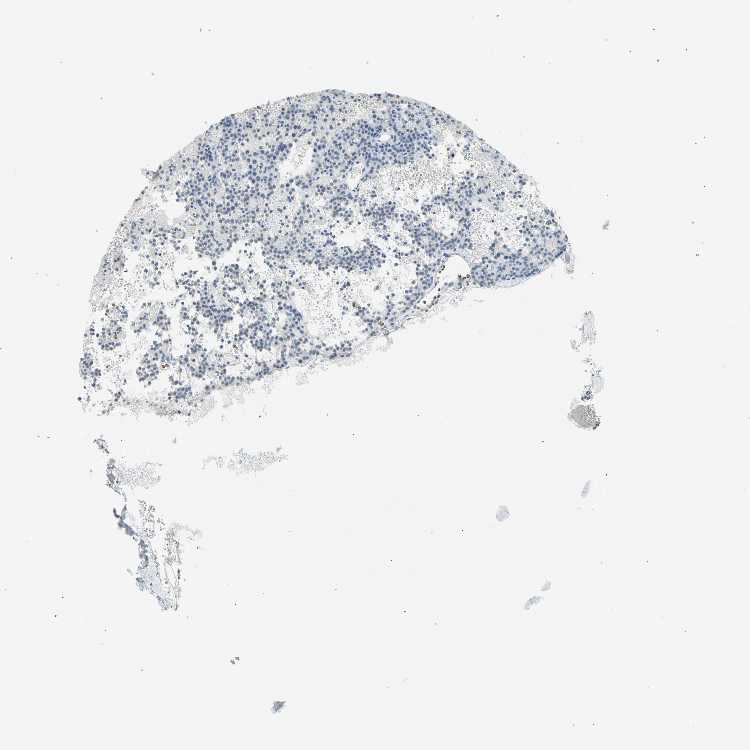

TISSUE PRIMARY DATA PARATHYROID GLAND Show tissue menu

PARATHYROID GLAND - Antibody stainingi

Antibody staining in the annotated cell types in the current human tissue is reported as not detected, low, medium, or high, based on conventional immunohistochemistry profiling in selected tissues. This score is based on the combination of the staining intensity and fraction of stained cells.

Each image is clickable and will lead to virtual microscopy that enables deeper exploration of all samples and also displays staining intensity scores, fraction scores and subcellular localization as well as patient and tissue information for each sample.

Antibody HPA005736Antibody HPA005747Antibody HPA072790

Glandular cells Not detectedNot detectedLow